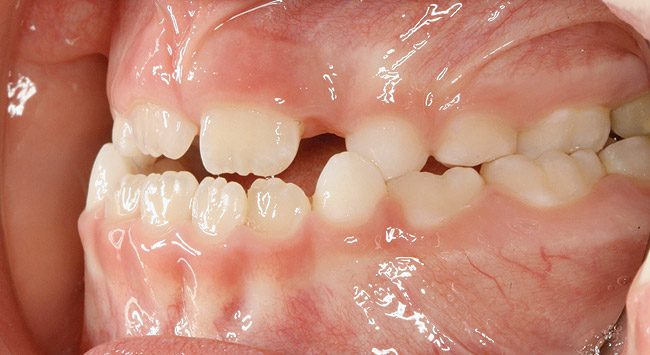

(10.) Narrow maxilla with tooth wear and bilateral crossbite.

Figure 10

(12.) Class II Angle classification with worn dentition and anterior open bite.

Figure 12